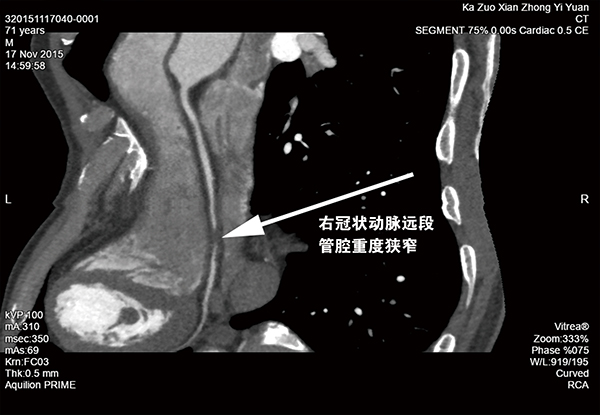

我院投巨资引进日本东芝AquilonPRIME CT(80排160层螺旋CT),是新一代高端多层螺旋CT机,具有扫描时间更短、成像更清晰、定位定性诊断更准确的特点。该机除具有普通螺旋CT功能外,在全身血管成像及三维图像后处理方面有显著优势,可对全身各种疾病进行全方位、多角度的直观、立体显示,极大地提高了早期、微小病变的检出率和复杂、疑难病变的诊断率特别是对心脑血管疾病可进行准确简便的无创性检查。

该仪器为世界一流诊疗设备,具有:最佳图像质量密度分辨率:最小的各向同性分辨率最高精度、细节分辨更清晰:最低扫描剂量的绿色环保;最快时间分辨率。